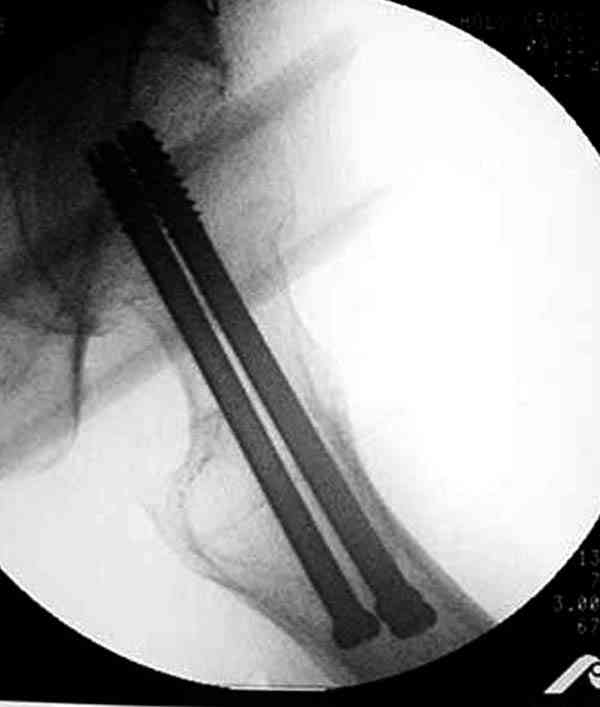

Коллега Челноков прав, здесь еще имеется риск перелома за счет ослабления латерального кортекса. Во время установки канюлированных шурупов за редким исключением спица вводится с одного раза, множественные попытки ослабляют латеральный кортекс, что станет источником перелома в этом месте.

В идеале для профилактики рефрактуры шурупы надо вводить не больше, чем под 130 градусным углом и не ниже уровня малого вертела.

Насчет биомеханических преимуществ одного шурупа тоже возникает вопрос. Если придерживаться канонов механики, для перелома шейки необходимо 3 паралельных шурупа, расположенных ближе к кортикальному слою шейки.

Здесь случай перелома из-за ослабления латерального кортекса через 3 недели после операции на шейке. Шурупы были установлены под большим углом, слабый латеральный кортекс не выдержал нагрузку.